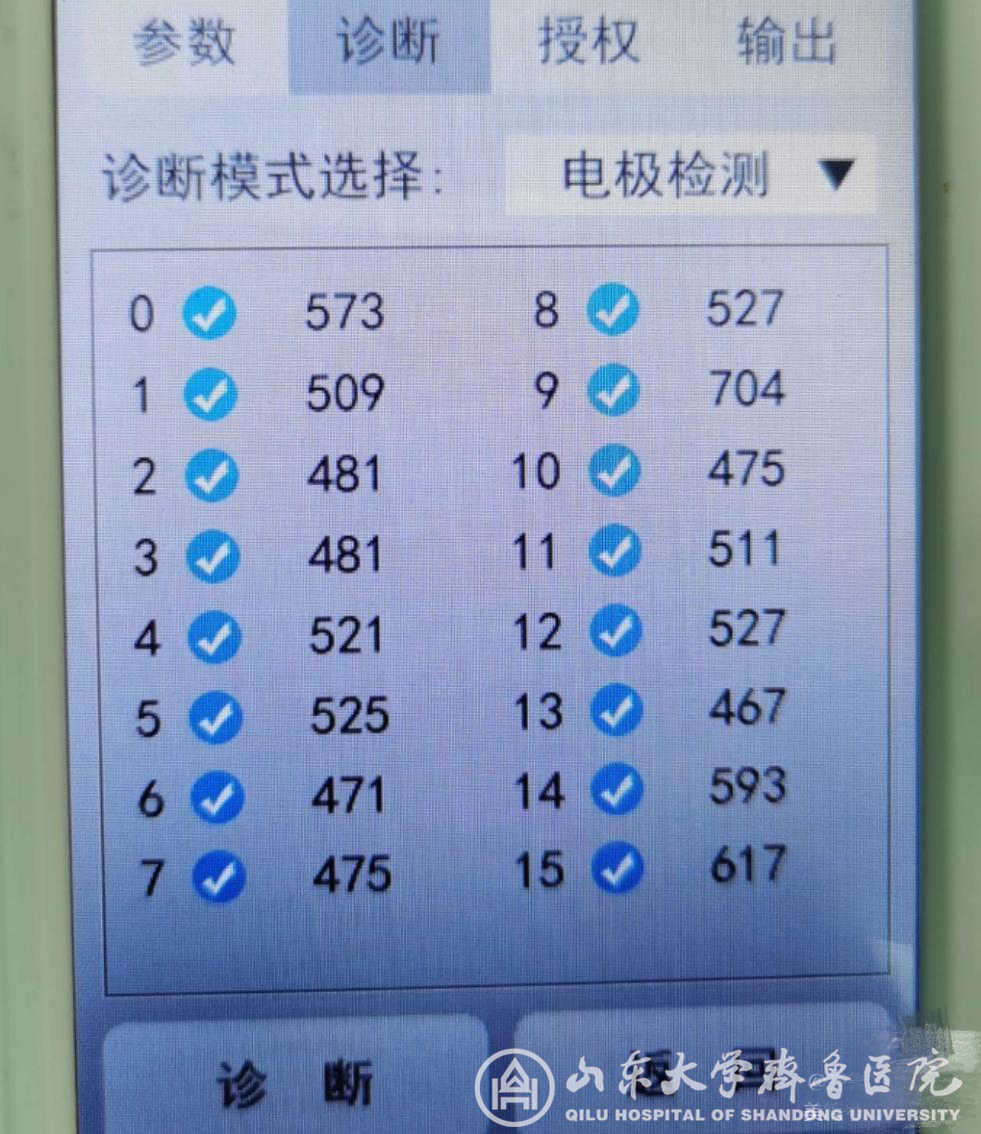

图2.颈髓损伤后顽固性疼痛患者术中穿刺植入针状电极

图3.电极测试良好